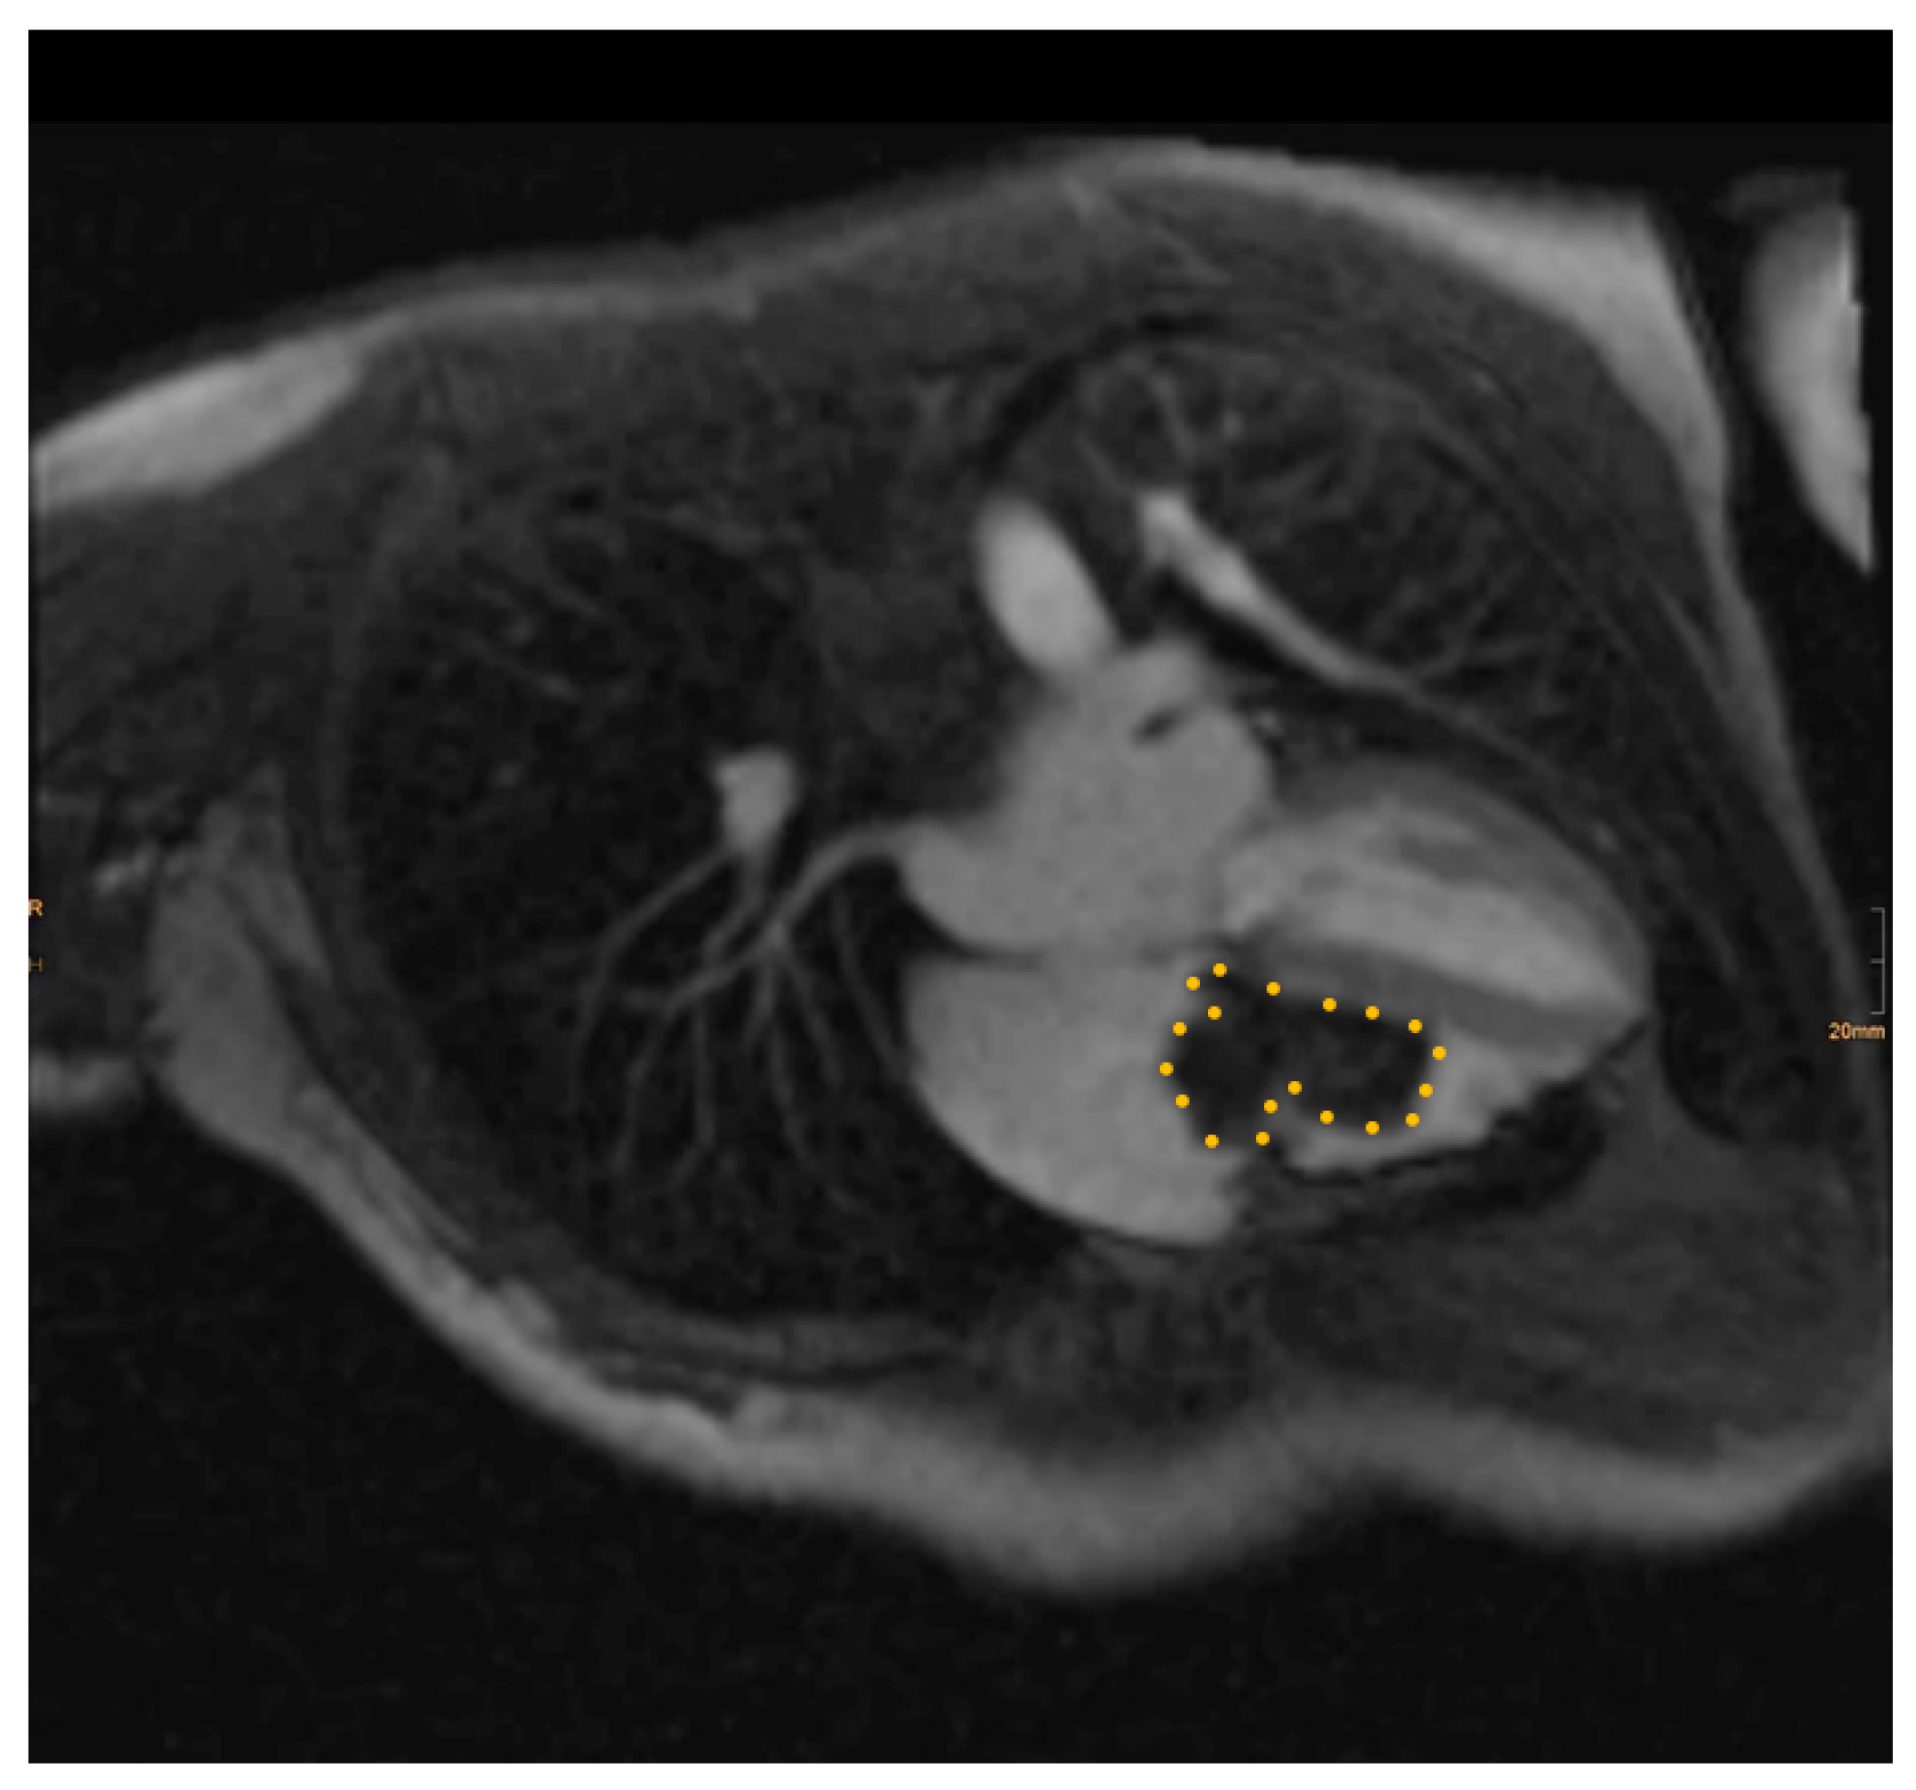

Pre-operative cardiac magnetic resonance imaging (MRI) and transesophageal echocardiogram (TEE) revealed a myxoma measuring 46 mm × 37 mm × 30 mm in the right atrium. The base of the myxoma, located around the basal posterior wall of the right atrium, appeared to extend to the tricuspid valve and right ventricle (Figure 1 and Figure 2). Despite the localization and considerable size of the myxoma, there was no significant tricuspid valve insufficiency, and the function of both the left and right ventricles remained within normal parameters. The patient was evaluated for open-heart surgery involving the removal of a myxoma, with consideration for tricuspid valve replacement.

Figure 1. Pre-operative transesophageal echocardiogram image. The myxoma boundaries are delineated with a dotted yellow line.

Figure 2. Pre-operative magnetic resonance image. The myxoma boundaries are delineated with a dotted yellow line.